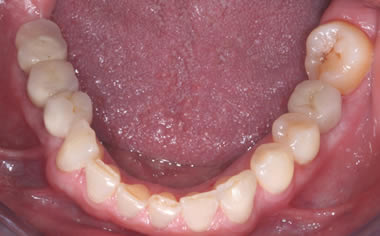

More back teeth replaced by dental implants

Case Three (2 images)